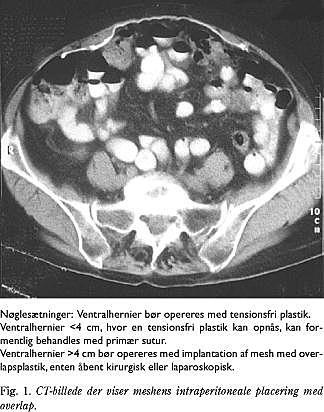

De seneste år har laparoskopisk herniotomi været anvendt med en intraperitoneal overlapsteknik, hvor meshen fæstnes mod peritoneum (Fig. 1 ). Der anvendes fra 3-5 trocharer oftest én på 10 mm og de øvrige på 5 mm. Variationerne ved den laparoskopiske procedure består i fiksering af meshen med henholdsvis coils, stabling eller suturer samt størrelsen af meshens overlap af bugvægsdefekten. I fire prospektive studier konstaterede man recidivrater på 1,8-9 % efter followupperioder på 7-27 mdr. (Tabel 3 ) (22-25). Fundene i de syv retrospektive studier afviger ikke væsentligt fra fundene i de ovenfor beskrevne prospektive studier med recidivraterne på 1-9 % efter 8-51 måneders followup (Tabel 3) (26-32).